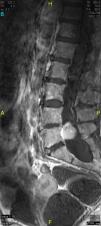

The patient underwent magnetic resonance imaging (MRI) of the low back, which revealed an intradural space-occupying lesion in the conus medullaris. It was hypervascularized and receiving its supply of blood from a rosary-like vessel,4 that extended from T10, occupying nearly the entire spinal canal to the level of L5. Spinal angiography confirmed the presence of a hypervascularized tumor irrigated by a medium-sized artery and a large, tortuous anterior spinal artery that was not amenable to embolization5,6 (Figs. 1–3).